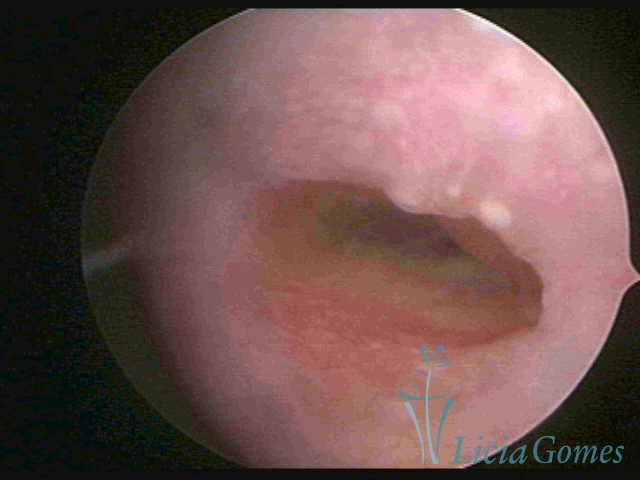

Segunda porção ou setor médio

No terço ou setor médio do canal cervical perdemos o detalhe das papilas, sendo possível a visualização de pregas e criptas. Normalmente observamos os sulcos longitudinais, que são os tecidos mais compactos, com a superfície mais vascularizada, cujos vasos seguem o seu trajeto.